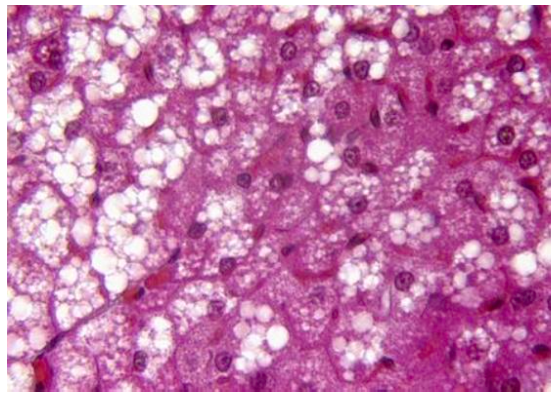

Concernant cette photo (trouvé dans les archives lointaines ...) il est dit que c'est du Tissu adipeux BRUN

MAIS, j'ai hésité en voyant la photo car certes on a cet aspect multiloculaire et des noyaux centraux

ON a aussi des grosses enclaves lipidiques du coup on dirait du TA Blanc de réserve JEUNE non ? Car je pensais qe le TA Blanc Jeune contenais à la fois des adipocytes avec noyaux centraux + adipocytes avec des noyaux en périphéries car les enclaves se remplissent de graisse